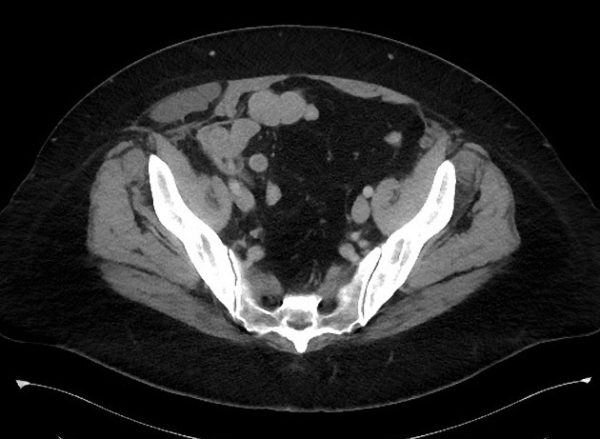

Thoát vị thành bụng

Thoát vị thành bụng - Ảnh 2

» Thông tin: Nữ giới – 50 tuổi.

» Lâm sàng: Đau hố chậu phải.